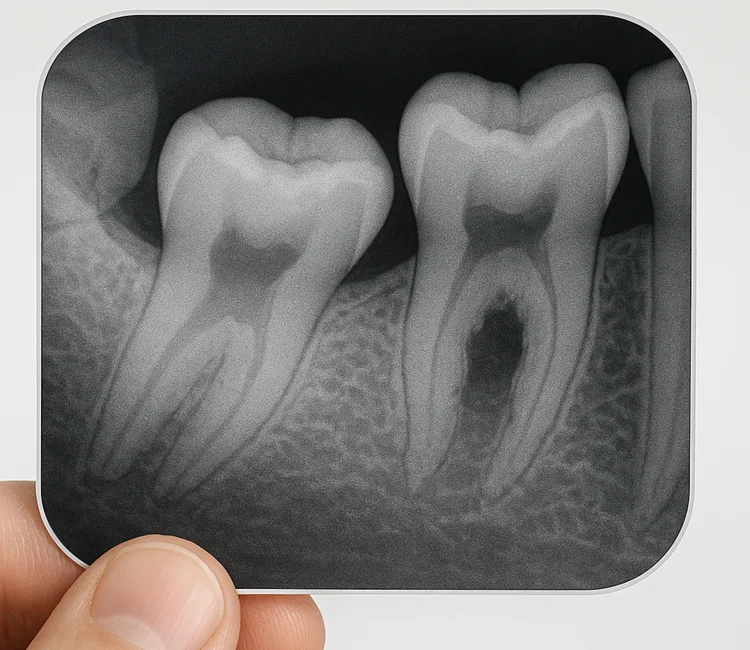

A constant, throbbing toothache is one of the clearest signs that you need urgent care. Pain that doesn’t respond to over-the-counter medication often indicates infection or nerve involvement. In many cases, treatment such as a root canal treatment is required to remove infection and save the tooth.

Sign #6: Signs of Abscess (Pus, Fever, Foul Taste)

A dental abscess is a pocket of pus caused by bacterial infection. Symptoms may include fever, a foul taste in the mouth, or visible pus around the gums. Antibiotics alone are insufficient; urgent treatment is necessary.

An untreated abscess can damage the surrounding bone and even lead to life-threatening complications if ignored.